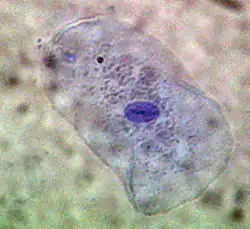

One of the most outstanding results of his dissertation investigations was the discovery of a new cell type. Ehrlich discovered in the protoplasm of supposed plasma cells a granulate which could be made visible with the help of an alkaline dye. He thought this granulate was a sign of good nourishment, and accordingly named these cells mast cells, (from the German word for an animal-fattening feed, Mast). This focus on chemistry was unusual for a medical dissertation. In it, Ehrlich presented the entire spectrum of known staining techniques and the chemistry of the pigments employed. While he was at the Charité, Ehrlich elaborated upon the differentiation of white blood cells according to their different granules. A precondition was a dry specimen technique, which he also developed. A drop of blood placed between two glass slides and heated over a Bunsen burner fixed the blood cells while still allowing them to be stained. Ehrlich used both alkaline and acid dyes, and also created new "neutral" dyes. For the first time this made it possible to differentiate the lymphocytes among the leucocytes (white blood cells). By studying their granulation he could distinguish between nongranular lymphocytes, mono- and poly-nuclear leucocytes, eosinophil granulocytes and mast cells.